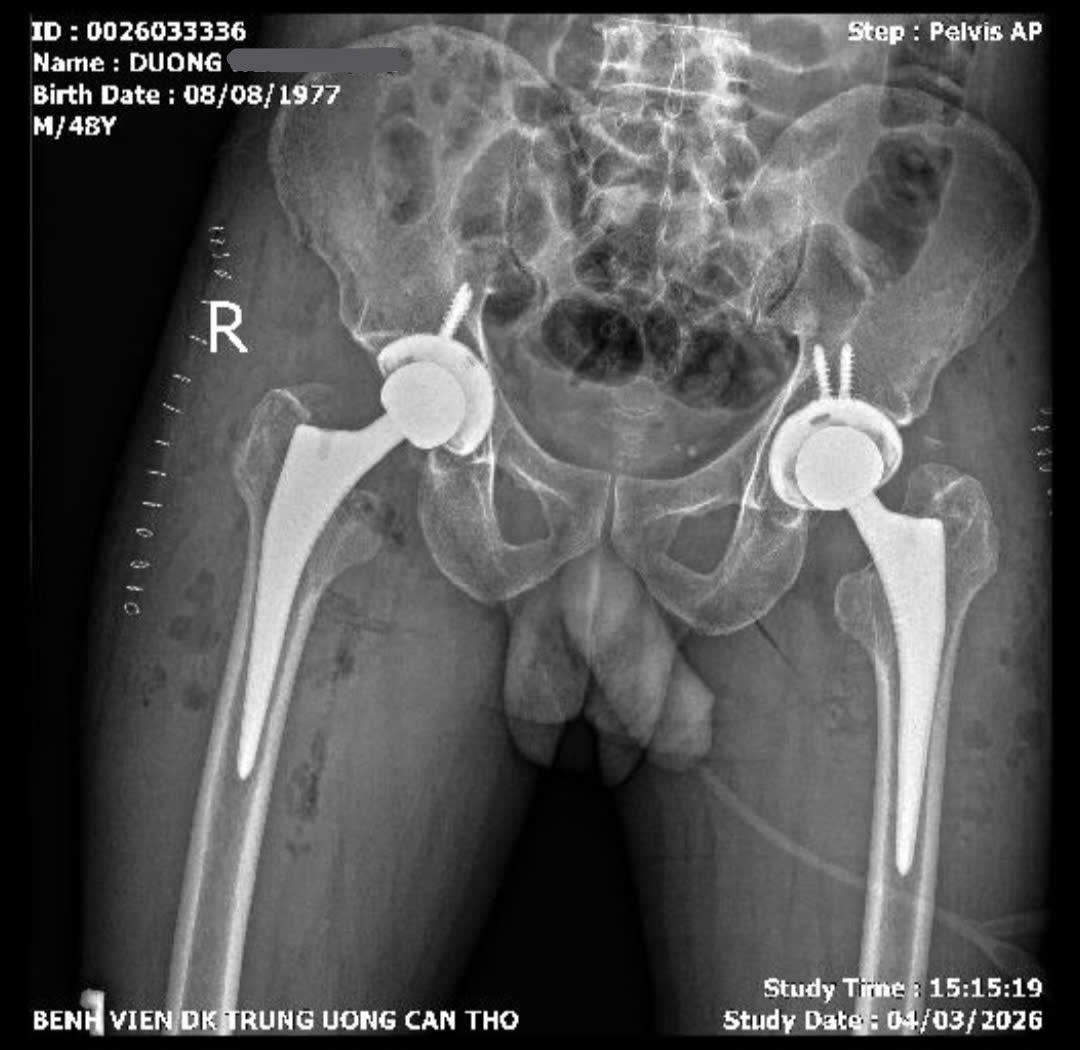

Các bác sĩ lựa chọn kỹ thuật thay khớp háng bằng đường mổ trực tiếp phía trước, một phương pháp ít xâm lấn hiện đại. Ca mổ kéo dài khoảng 4 giờ và tiến hành thay khớp háng hai bên trong cùng một lần phẫu thuật.

Sau phẫu thuật, bệnh nhân phục hồi tốt. Đến ngày thứ hai đã có thể tập đi với khung hỗ trợ và sau 5 ngày có thể tự đi lại không cần dụng cụ hỗ trợ. Bệnh nhân dự kiến xuất viện vào ngày 11/3.